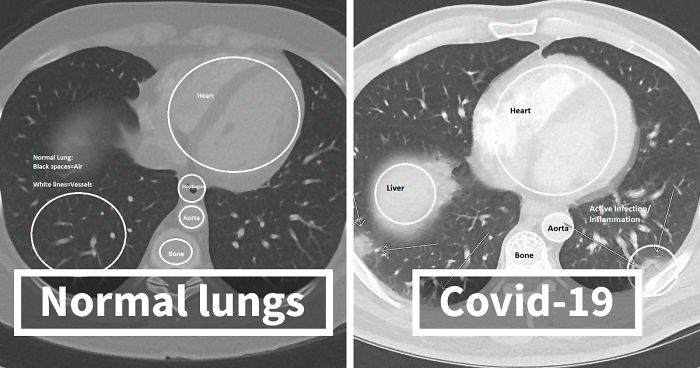

Imgur user and radiologist HeyYoMikey8 said the unknown future is the hardest part of the coronavirus pandemic. HeyYoMikey8 believes it is our own responsibility to educate ourselves so we can all do our part during these difficult times. So, to make it easier for us, the health professional shared what they’re seeing in cases of Covid-19 radiographically. The comprehensive commentary, as well as images used to help in the diagnosis and managing complications or evaluating the progression of the disease, should definitely broaden your understanding of what we’re all facing.

Interestingly, in the early days of the coronavirus outbreak, radiological imaging was not regarded as a way to confirm evidence for COVID-19 cases. Instead, authorities relied on a positive result of the PCR nucleic test. The supply of the PCR test kits, however, was limited and getting back the results took a long time. So, Chinese health authorities soon recognized these difficulties and changed the diagnostic strategy in their 5th edition of the Guidelines on Diagnosis and Treatment of COVID-19. As a result, radiological features of COVID-19 were included as one of the three determinant clinical manifestations to confirm a suspicious patient. The high efficiency, reliability, and accessibility of the radiological diagnostic technology have helped tremendously in identifying the disease. These processes were soon enhanced further by the introduction of artificial intelligence (AI) algorithms.